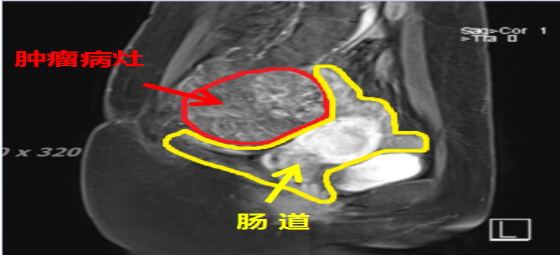

患者王**,女性,52岁,黎族,诊断:骶尾部脊索瘤。治疗前评估:MR-骶2-4椎体部分骨质破坏,相应平面见大小约8.8x7.1cm(S6,I57)混杂T1、混杂长T2肿块影,向盆腔内生长,局部侵及骶管,边界尚清;病灶约270度的范围内紧临结直肠。

2023年3月(碳)离子治疗前核磁检查,红圈内为肿瘤

2023年3月(碳)离子治疗前核磁检查,红圈内为肿瘤

治疗前肿瘤8.8×7.1cm,左图为MRI的T1轴位,中图为T2轴位,右图为T1矢状位